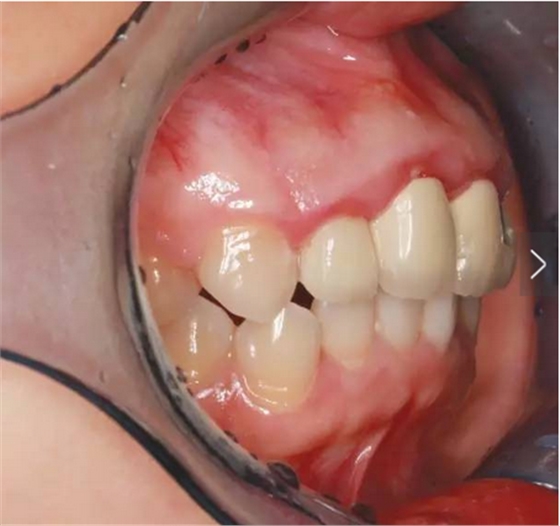

臨床檢查可見12~22烤瓷聯(lián)冠修復(fù),冠邊緣不密合,齦緣外形不協(xié)調(diào),牙齦紅腫,22烤瓷冠崩瓷。根管治療不完善,牙齦根尖部位有瘺管,X線影像顯示11、21根尖有陰影。上頜前突,上前牙修復(fù)體舌傾。 患者治療前口內(nèi)像 側(cè)位像 治療前曲面體層片 治療前前牙區(qū)X線片